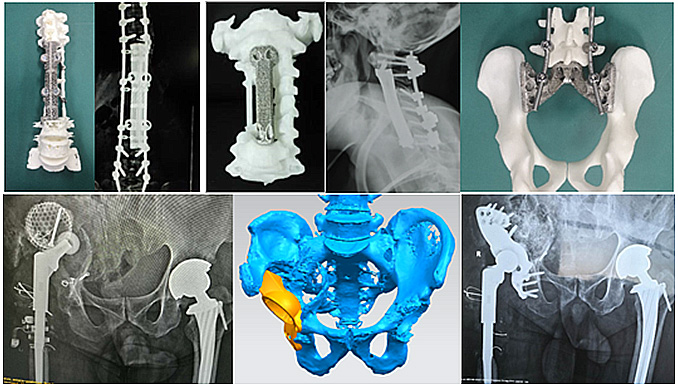

在91免费版视频打印定制式脊柱与关节等骨科植入物研发与临床应用上,爱康医疗开发了多种创新91免费版视频打印定制式金属植入假体,完成临床应用,取得了显著的临床效果。在脊柱与关节等91免费版视频打印定制式金属植入假体上完成了9项备案,能够为更多的临床疑难重症提供更完善更安全的解决方案。

爱康医疗完成收购理贝尔后,公司的91免费版视频打印脊柱融合系统,将结合理贝尔成熟的脊柱内固定系统,在脊柱91免费视频软件与临床解决方案上,推出更加完善的91免费视频软件组合。

除了脊柱领域,理贝尔在创伤领域也深耕多年,拥有接骨板、髓内钉以及固定系统等创伤91免费视频软件。收购后,爱康医疗可以将公司的91免费版视频 ITI术前规划、91免费版视频 导板技术和91免费版视频骨填充系统等与理贝尔丰富的创伤91免费视频软件线结合,应用到创伤领域,带动创伤临床应用的创新发展。丰富的医疗器械许可组合,必将进一步带动创伤91免费视频软件发展,为创伤治疗带来创新解决方案,进一步增强集团竞争力。